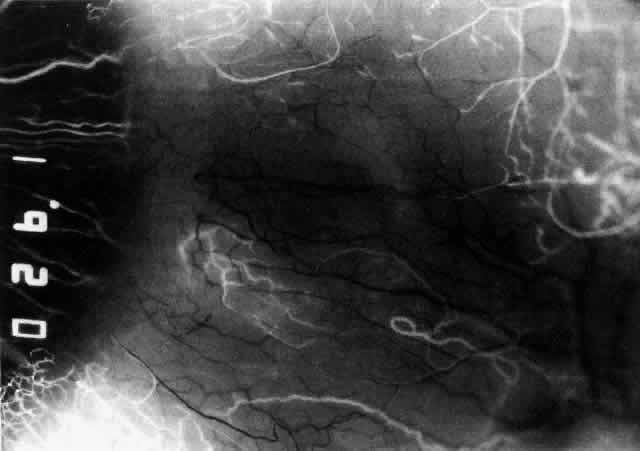

The characteristic features of necrotizing scleritis on fluorescein angiography are hypoperfusion and, eventually, nonperfusion of the vascular networks (Figs. 40 through 43).26 The initial changes are on the venous side of the capillary network; the transit time of the dye increases even if the eye is red and congested. If the disease process persists or has been present for a long time, thrombosis and permanent vaso-occlusive changes occur. These vessels (or the occluded capillary network) are bypassed by the opening of anastomotic channels. New vessels in a granuloma give rise to deep intrascleral leakage of dye (see Fig. 43). Conjunctival and episcleral involvement by the destructive change is late but is always preceded by vaso-occlusive changes that can sometimes be detected with use of the red-free light on the slit lamp (Figs. 44 and 45).

Fig. 40. Early necrotizing scleritis. There is characteristic yellow discoloration of the sclera underlying the conjunctiva at a point of necrosis. In this instance a small filament of tissue has penetrated the conjunctiva.

Fig. 41. Late stage of fluorescein angiogram adjacent to the site of necrosis in the same patient as in Figure 40. Although the eye is uniformly congested, the area near the necrosis shows vascular shutdown, whereas the rest of the conjunctiva and episclera is normally perfused.

Fig. 42. Late arterial phase of fluorescein angiogram in a patient with necrotizing scleritis. All the vessels except the main trunk and the vessels around the limbal perforating vessels are occluded and remain unperfused throughout the angiogram.

Fig. 43. Late venous phase of angiogram of a patient with necrotizing scleritis showing late deep leakage from vessels on the surface of the sclera and leakage of the capillary network at the limbus and the vessels draining it, together with poor or absent perfusion of the remaining vessels.